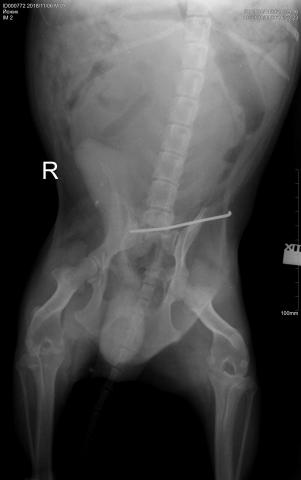

Рентген,перелом между

Рентген,перелом между последним поясничным и крестцовым.